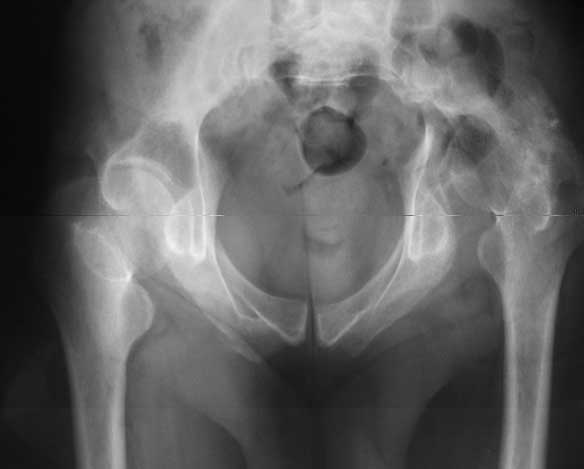

Dear All, The patient came to us for opinion regarding this # of pelvis which he sustained 5 months back.

He gives history of being on skin traction for 3,5months. After that he was advised partial weight bearing to be graduated to full weight bearing. Now the patient has difficulty in weight bearing as it is painful. He can walk a few steps only with the help of a walker. Hip movements are restricted and painful. Fl-90* ER-10* IR-0, shortening-4cm. He also had # of humerus and radius/ulna, which were plated and have united. The serial x-rays of the pelvis/Hip during these 5 months show that the hip joint has been in the same position. I have the CT pictures also but not digitalized as yet.

It is a displaced and ununited fracture of the acetabulum, probably type C (AO). The pelvis is not fractured from what one can see of the sacro iliac joint.

Sorry missed the wide open pubic diastasis.